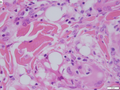

- The layer below the skin is the subdermis (AKA hypodermis, AKA subcutaneous tissue).

- It is below the dermis and consists of adipose tissue.[3]